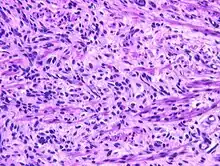

Fetal rhabdomyoma are separated into two histologic types: Myxoid and cellular.[7][8] However, irrespective of histologic type, these tumors almost never show necrosis or increased mitoses. However, a cambium layer, abnormal mitoses and nuclear pleomorphism is not seen.

Cellular fetal rhabdomyomas are composed of bland, primitive spindled cells. The spindle cells are haphazardly arranged primitive, elongated skeletal muscle cells. The cells are set within a well-developed fibromyxoid stroma. A different pattern (intermediate type) is predominantly composed of cells with better differentiation towards skeletal muscle. There are often large ganglion cell-like rhabdomyoblasts showing prominent nucleoli within nuclei that show vesicular chromatin distribution. Another population includes strap-like rhabdomyoblasts with darkly staining pink cytoplasm. Nearly all tumors show short to more sweeping fascicles of spindled rhabdomyoblasts. The tumor cells may infiltrate into adjacent skeletal muscle or fat. It is not uncommon to see peri-neural association, although not perineural infiltration.[9]